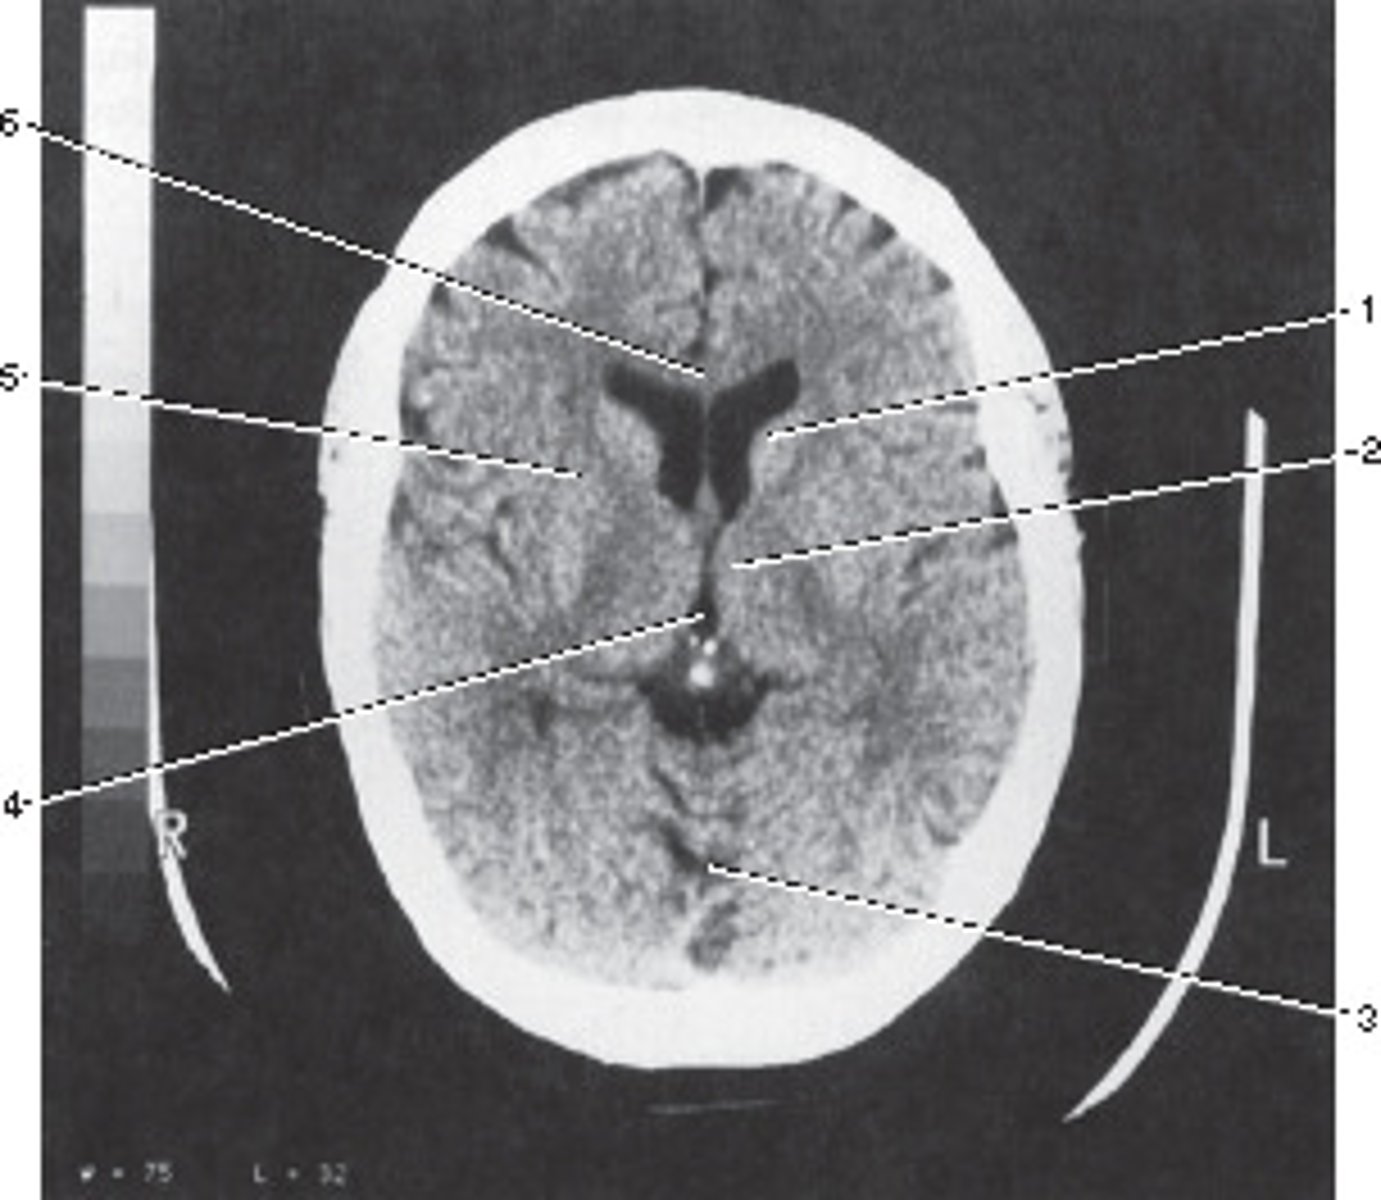

Third Ventricle

Number 4 corresponds to which of the following?

<p>Number 4 corresponds to which of the following?</p>

28

New cards

Genu of the Carpus Callosum

Number 6 corresponds to which of the following?

<p>Number 6 corresponds to which of the following?</p>

29

Vein of Galen

Identify structure B on this axial CT slice of the brain.

<p>Identify structure B on this axial CT slice of the brain.</p>

82

Internal cerebral veins

Identify structure C on this axial CT slice of the brain.

<p>Identify structure C on this axial CT slice of the brain.</p>

83

Thalamostriate vein

Identify structure D on this axial CT slice of the brain.

<p>Identify structure D on this axial CT slice of the brain.</p>

84

Straight sinus

Identify structure E on this axial CT slice of the brain.

<p>Identify structure E on this axial CT slice of the brain.</p>

85